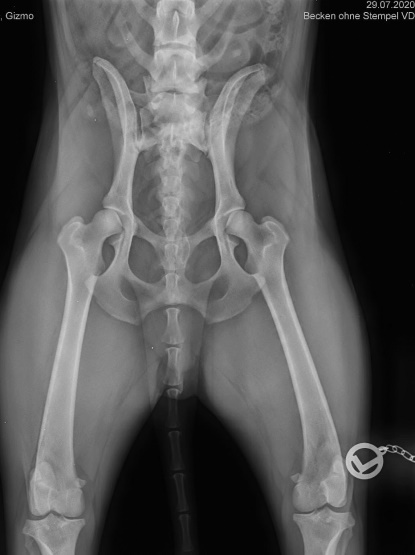

Beim Betrachten des Bildes wurde unser Tierarzt aber stutzig. Er zählte und zählt mehrmals und fand dann raus, dass Gizmo einen Übergangswirbel hatte.

Hier nun noch die beiden Röngten von Gizmo wo der Übergangswirbel zu sehen sei, wo mich hier besonders interessiert, ob ihr den zum Einen auch seht und zum Anderen, welche Stufe von Übergangswirbel das wohl ist - 0 bis 3?